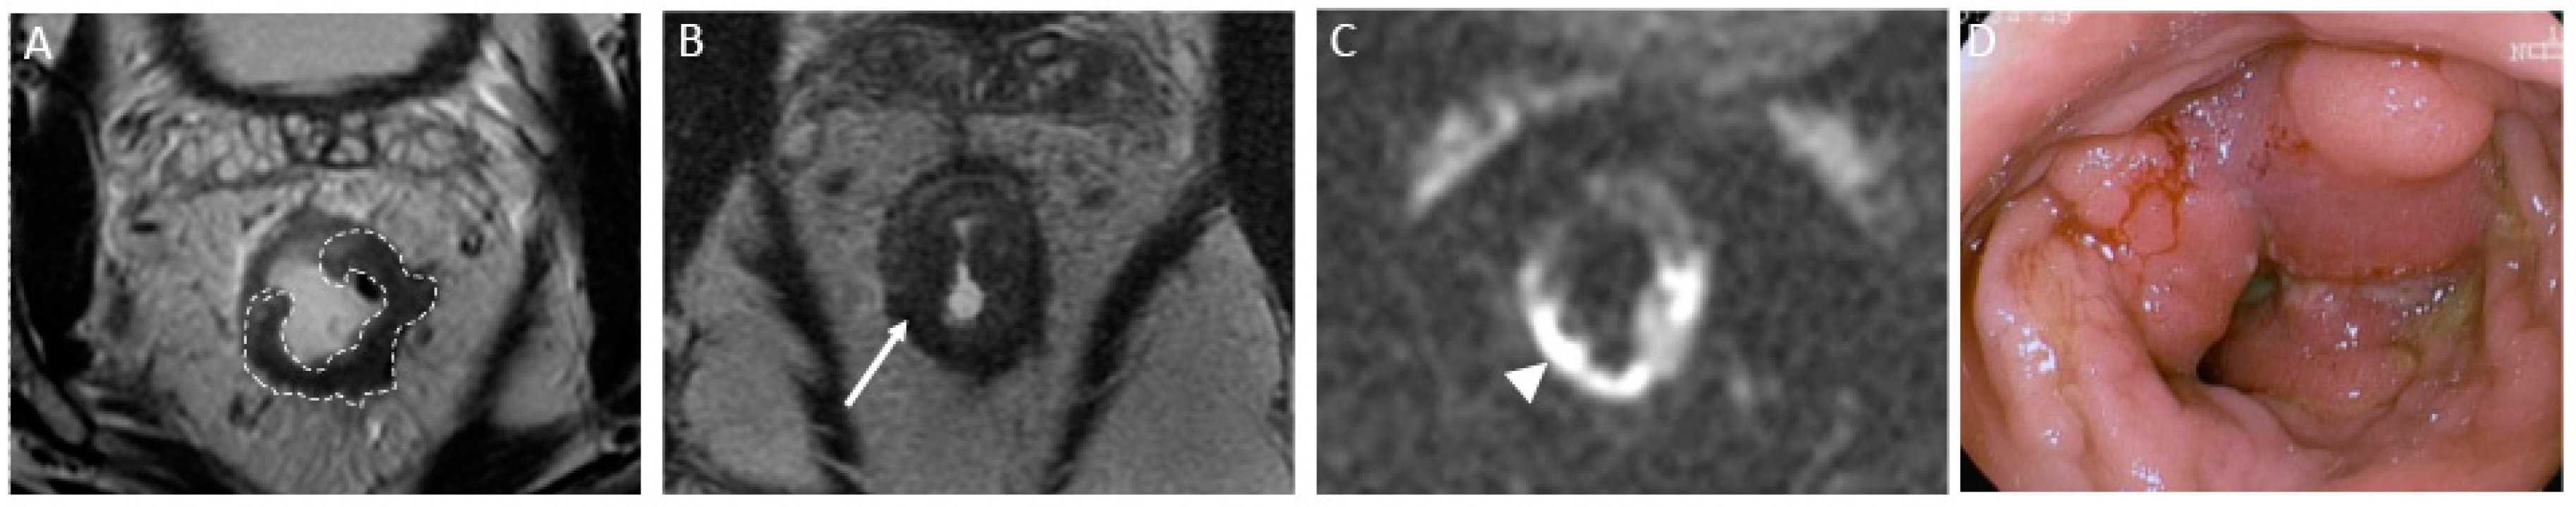

- nCR serves as a transitional state between CR and other responses, with substantial regression evident. Of note, the term nCR emerged only recently, driven by the observation that a significant proportion of patients who display very good yet incomplete responses during the first assessment do ultimately achieve a CR when provided with a longer interval before re-assessment (26) (Figure 3). nCR retains a trace of diffusion restriction post-neoadjuvant therapy, underscoring ongoing positive changes. In cases where tumor signal or diffusion restriction persists after one or two short-term follow-up evaluations, the case should be reclassified as iCR and considered unsuitable for observation.

Figure 3.

Near-complete response in a 65-year-old man with middle rectal adenocarcinoma. (A) Baseline axial T2-weighted MR image shows an intermediate-signal-intensity, near-circumferential low rectal tumor (dotted line). (B) Axial T2-weighted MR image after the completion of neoadjuvant chemoradiotherapy shows a slight response with a small amount of fibrosis and residual tumor signal intensity (arrow). Axial diffusion-weighted image (C) shows high signal intensity (arrowhead), and the axial apparent diffusion coefficient map (D) shows a corresponding low signal intensity (arrowhead), in keeping with restricted diffusion at the nonfibrotic portion of the tumor.